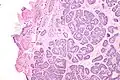

Micrograph of a Sertoli cell nodule. H&E stain. -

A Sertoli cell nodule is a benign proliferation of Sertoli cells that arises in association with cryptorchidism (undescended testis).[1] They are not composed of a clonal cell population, i.e. neoplastic; thus, technically, they should not be called an adenoma.[2]

Sertoli cell nodules are unencapsulated nodules that consist of:[2][3][4]

- cells arranged in well-formed tubules (that vaguely resemble immature Sertoli cells), with

- bland hyperchromatic oval/round nuclei that are stratified, and

- may contain eosinophilic (hyaline) blob in lumen (centre).